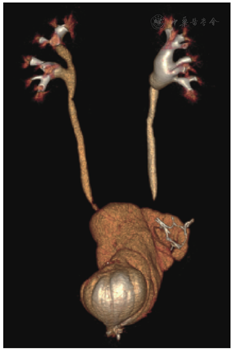

术后随访3个月,患者日间可完全控尿,夜间需0~1块尿垫。排尿间隔为3.5 h,每次排尿量平均350 ml。尿动力学检查示膀胱顺应性正常,容量365 ml,无残余尿。B超检查示患者双肾轻度积水,排尿后可缓解。复查血肌酐71μmol/L。CTU检查(图2)未见肿瘤复发表现。患者术后满意度高,基本恢复正常生活。因患者术后病理提示转移淋巴结阳性,予吉西他滨联合顺铂辅助化疗。

双肾盂输尿管无明显扩张积水,双肾盏杯口好,膀胱充盈好,形态符合新膀胱表现